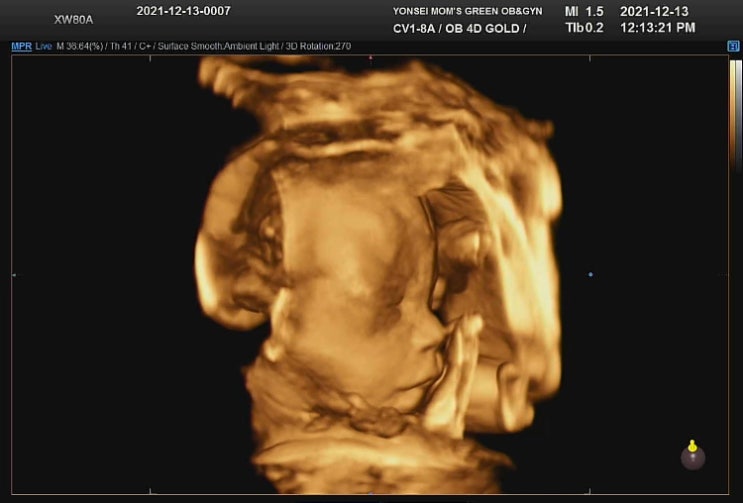

25주 임산부 임당검사, 첫째와 둘째 입체 초음파 실물 비교, 일산 차병원

지난 12월 22일 정기검진 기록 25w5d 임신당뇨 검사 (임당) 정말 너무너무 빨리 지나가는 둘째의 임신기간....